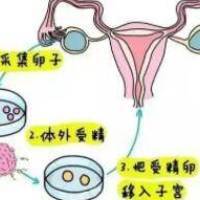

最近在生殖中心接诊时,32岁的李女士着急地问我:"医生,我AMH值只有1.2,做试管取卵两次都配不成优质胚胎,是不是我的卵子质量太差了?还能补救吗?"其实很多试管姐妹都面临类似困扰——卵子质量直接决定胚胎发育潜力。今天就从专业角度教大家如何针对性调理。

优质卵子需要具备正常染色体、充足能量和完整结构。临床上常见的问题包括:取卵后受精率低、胚胎碎片多、养囊失败率高。这往往与年龄增长、内分泌紊乱(如甲减/多囊)、长期熬夜、接触有毒物质(染发剂/新装修环境)等因素相关。